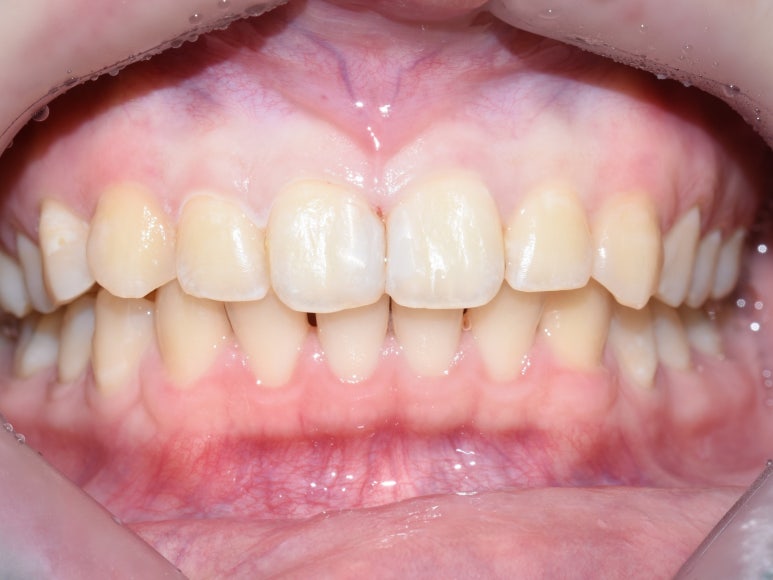

오늘은 저희 치과에서 치료한

앞니 사이 충치치료 레진 케이스를 살펴보고자 합니다.

앞니사이 충치치료 레진치료

지금까지 시청역 연세예감치과에서 알아본

앞니 사이 충치치료를 위한 레진 전 - 중 - 후 모습이었습니다.